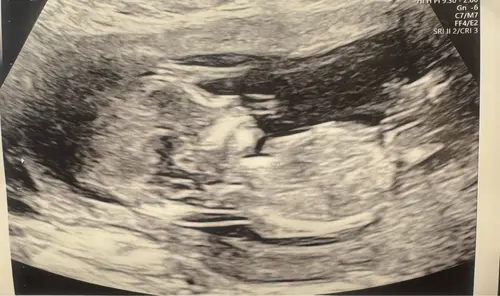

Kan je toevallig hierin wel wat zien haha?

Deze had je keertje al geposted hihi, ik denk wel jongen